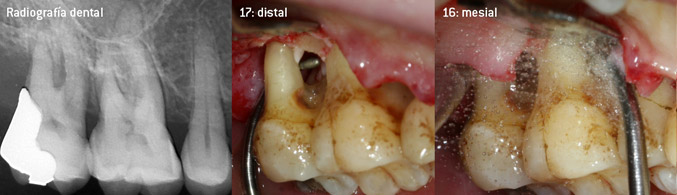

Como precursores del desarrollo de la nueva punta diamantada 3AP para eliminadores de sarro neumáticos, los dos odontólogos constataron que era necesario limitar el uso de las puntas diamantadas que se estaban comercializando hasta la fecha, sobre todo durante los tratamientos de furcaciones o en bolsas interradiculares estrechas. Además, esto debe llevarse a la práctica independientemente de si se trata de un procedimiento no quirúrgico (figura 2) o de un procedimiento quirúrgico (figura 3).

Fotos (figuras 2 -4): © Dr. Christian Graetz)

El objetivo principal consistía en desarrollar una punta de uso universal para no tener que perder tiempo al cambiar de punta de un tratamiento a otro. No obstante, también se pretendía que el uso de las nuevas puntas fuera más sencillo, tanto en bolsas periodontales estrechas desde el lado distal como en la entrada de furcaciones distales en los molares superiores, de manera que el tratamiento con instrumentos resultara más eficaz. Esto se consiguió aumentando el diámetro del arco del instrumento (figura 1), lo que representa una enorme ventaja durante el desbridamiento cerrado, sobre todo en el caso de piezas dentales con pérdida de adherencia avanzada y lesiones de furcación (figura 4).